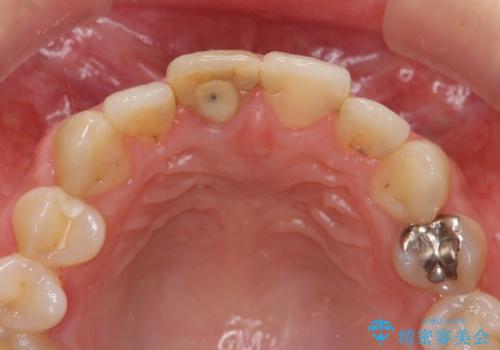

前歯 審美改善セラミック治療

- 前歯の見た目、変色の改善を希望され来院されました。

ジルコニアクラウンによる審美性の改善を計画します。

神経の治療をした歯について

神経をとる治療を行った歯は、時間が経過すると術前のように変色し見た目を大きく損ないます。

このような場合金属を使わないジルコニアクラウンを用いた治療を行うことで天然の歯のように審美性を改善することが可能になります。